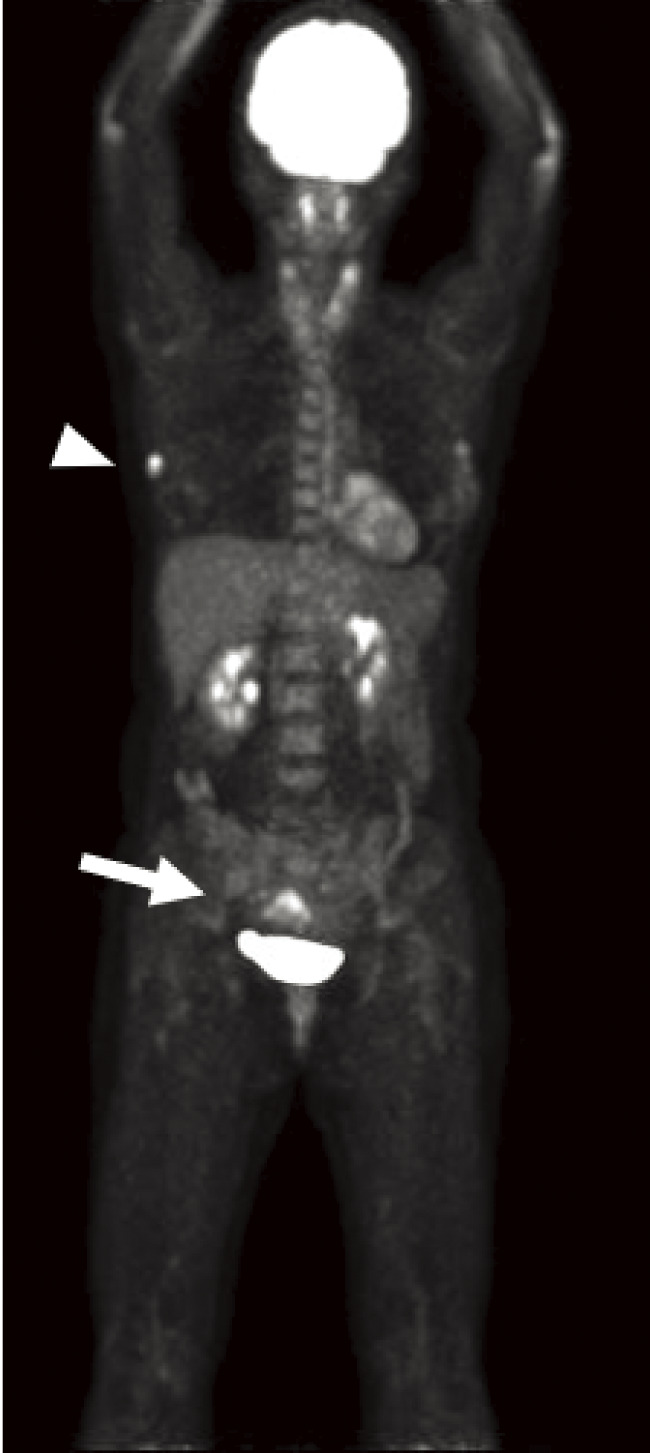

Case presentation: We describe the case of a 44-year-old female patient with invasive ductal carcinoma of the right breast. Cobblestone papillomatosis was present in the gingiva. She had a medical history of bilateral adenomatous goiters for 10 years. Her mother had been diagnosed with breast cancer, thyroid and tongue tumors, gastric polyps, hepatic hemangioma, and collagen disease. Additionally, the patient's maternal grandmother had a history of colon cancer. Based on the patient's family history and physical findings, CS was suspected, and direct DNA sequencing analysis revealed a haplotype c.634del mutation in exon 7 of the PTEN gene. Although there is no clear evidence supporting risk-reducing surgery for PHTS, a right nipple-sparing mastectomy, sentinel lymph node biopsy, and tissue expander reconstruction were performed.